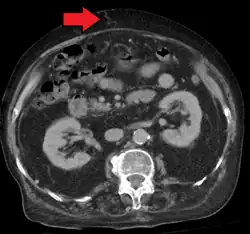

In addition, a widened (dilated) portal vein as seen on a CT scan or MRI may raise the suspicion about portal hypertension. A cutoff value of 13 mm is widely used in this regard, but the diameter is often larger than this is in normal individuals as well.[9]

Ultrasonography (US) is the first-line imaging technique for the diagnosis and follow-up of portal hypertension because it is non-invasive, low-cost and can be performed on-site.[17]

A dilated portal vein (diameter of greater than 13 or 15 mm) is a sign of portal hypertension, with a sensitivity estimated at 12.5% or 40%.[18] On Doppler ultrasonography, a slow velocity of <16 cm/s in addition to dilatation in the main portal vein are diagnostic of portal hypertension.[19] Other signs of portal hypertension on ultrasound include a portal flow mean velocity of less than 12 cm/s, porto–systemic collateral veins (patent paraumbilical vein, spleno–renal collaterals and dilated left and short gastric veins), splenomegaly and signs of cirrhosis (including nodularity of the liver surface).[17]